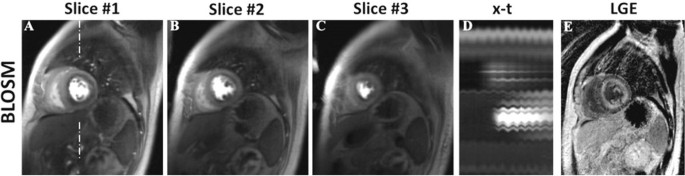

Figure 1 shows example BLOSM and k-t SLR reconstructed images from one slice at multiple time points. This example demonstrates that with prominent respiratory motion (see the x-t profiles in (D) and (H)), BLOSM (A-D) provides consistently good image quality, while k-t SLR (E-H) shows blurring (E,F). Figure 2 shows BLOSM results from three slices from a patient with a perfusion defect and prominent respiratory motion (D), along with a corresponding LGE image showing scar (E). Image quality scores were better for BLOSM (2.1±0.8 for BLOSM vs 2.9±0.7 for k-t SLR, p<0.01).

Example BLOSM reconstruction results from one patient with amyloidosis. Multi-slice images from one time point are shown (A-C), along with the x-t profile (D) and a corresponding LGE image (I). A subendocardial perfusion defect is clearly depicted by BLOSM, even in the presence of respiratory motion during the scan, as illustrated in the x-t profile. The subendocardial perfusion defect location matched closely with enhancement on the LGE image.